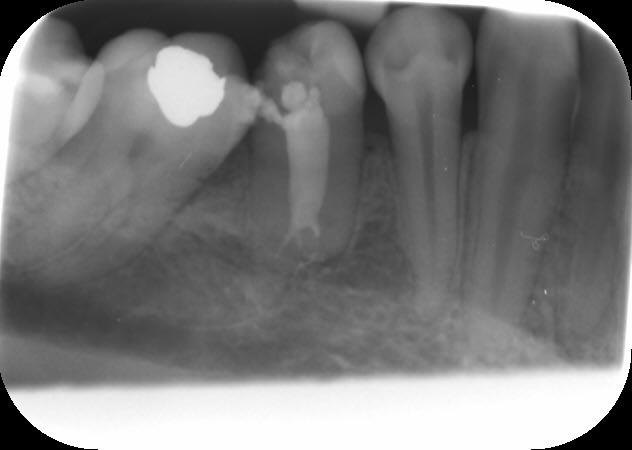

Bon...on va attendre 6 mois avant de dire qu'il n'y a pas de soucis. La difficulté ici était le lentulo fracturé coronairement qui n'autorisait pas le by-pass (au départ, parce que je lui ai expliqué qu'il fallait qu'il se pousse pour me laisser passer et il a été gentil, il m'a obéit :-))

En fait, ça ne se voit pas sur la radio d'eugenol (perte de qualité) mais il y a un lentulo dans l'obturation du canal MV (et un autre au niveau apical que l'on voit ici).

Pour répondre à dumaille : oui. Si tu regardes bien la radio postop, tu verras des trabécules osseuses juste sous la furcation. Le sondage était normal aussi bien en lingual qu'en vestibulaire. La lésion étant fermée, il n'y a aucune raison qu'en cas de succès apical il y ait une persistance radioclaire entre les racines.

Pour Aymen : Une fois le by-pass réalisé, Dominique Martin conseillait il y a quelques années dans une conférence de la SOP de rester en manuel avec les instruments NiTi. Je ne sais pas s'il s'applique ça à lui même ou si c'était un conseil destiné aux praticiens lambdas. Personnellement, je prend souvent ce risque (si je sens intuitivement en fonction du cas que je peux le faire, et si j'ai le moindre doute, je pense à mon ami Willy qui me disait un jour "si tu te poses la question, ne le fais pas !" Je pense d'ailleurs souvent à lui à cause de ça car il y a plein de situations cliniques où je me pose des questions. Dans le cas présenté, j'y suis allé en rotation mécanique justement. L'instrument fracturé coronairement à été enlevé après la mise en forme. Il faut bien comprendre qu'ici, ce fragment était un lentulo. Si ça avait été un protaper F2 par exemple, je serai sans doute rester en manuel, en fonction des sensations tactiles avec le dernier instrument acier utilisé (ici une lime K15).

Pour l'obturation, je ne vois aucune raison de changer quoique ce soit à cause d'un fragment d'instrument qui resterait en place. Une technique à chaud me parait cependant idéale pour enrober le fragment. Dans le cas présent, c'était thermafil et la courbure apicale en était une excellente indication à mon avis.